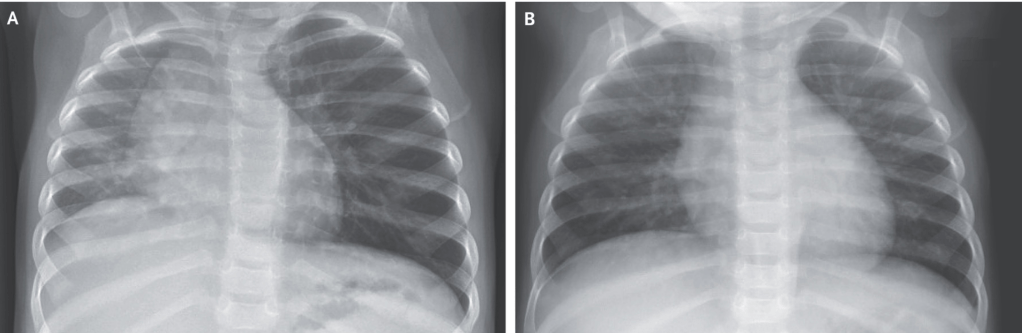

Pigtail Catheter vs Large Bore Chest Tube for Pneumothorax

- We agree with the author’s conclusion. PC performed as well as LBCT in terms of successful drainage and was associated with fewer complications, decreased drainage duration, and decreased length of hospital stay, driven by data on spontaneous pneumothorax.